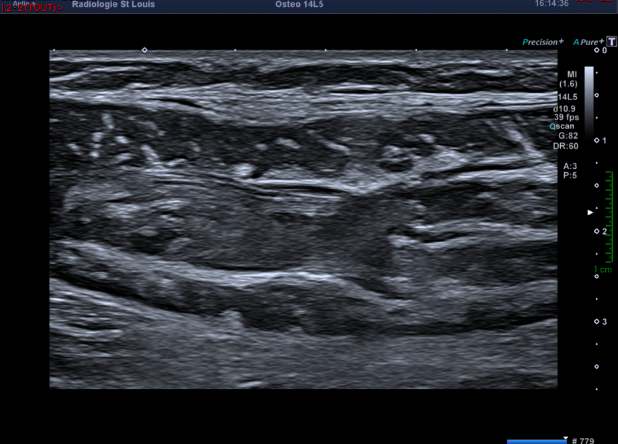

Cependant le regard de l’échographiste s’arrête sur cette image.

Que vous évoque cette collection liquidienne située entre les muscles gastrocnémien médial et soléaire ?

Il s'agit d'un hématome lié à la désinsertion myoaponévrotique au niveau de la jonction  des muscles gastrocnémien médial et soléaire, compatible avec un tennis leg.

La douleur que cette lésion musculaire provoque au mollet peut mimer une thrombose veineuse des membres inférieurs en raison de sa localisation.